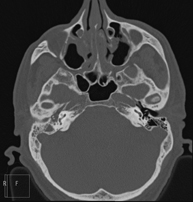

Ear CT

Radiological test that provides high definition anatomical images of the ear (internal and external auditory canal, eardrum, ossicles of the ear), using CT (Computed Tomography) equipment. Indicated for: hearing disorders, vertigo, dizziness, tinnitus (ringing).